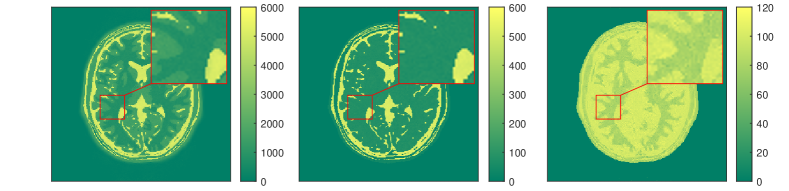

We present some numerical examples in Figure 12, where we compute solutions of the optimization problem (3.36). In this example, the neural network simulating the Bloch map is trained via a training set which was obtained through discrete dynamics of simulated Bloch data. In particular, a set of parameter pairs in the feasible domain of and is taken as inputs of the network, and then the simulated Bloch dynamics resulting from all these pairs are regarded as the outputs. The simulated k-space data in this example are generated using exactly the same setting as the one used for Figures 3 and 4. For such a discrete time series, the Bloch map is a Nemytskii type operator, and thus can be approximated sufficiently well in a uniformly bounded feasible set.